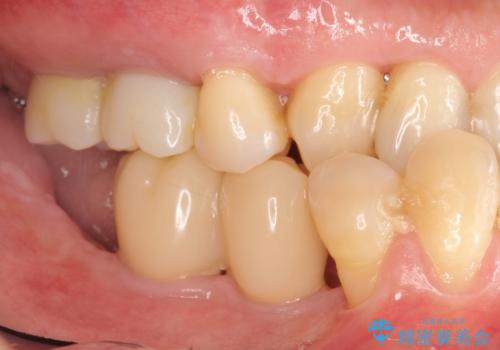

インプラント治療を併用した全顎歯周病治療

工程も多く、治療期間も長くなりがちですが、しっかりと通っていただいたおかげで安定した噛み合わせで食事を楽しむことができるようになりました。

メンテナンスも定期的に行うことで安定した状態を保っています。